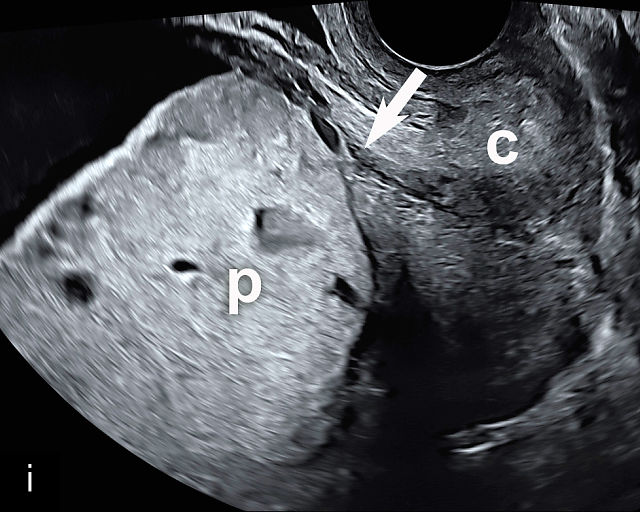

5

Placenta previa and low-lying placenta. (a) Transabdominal grayscale ultrasound image suspicious for placenta previa. The placenta (PL) appears to overlie the internal cervical os (CX). Note the time stamp: 2:19:37. (b) Transvaginal ultrasound of the same patient taken approximately 50 minutes later. Note the time stamp: 3:10:25. The internal os and the lower placental edge are both clearly seen, and the placenta does not overlie the internal os. Because the lower placental edge is 1.93 cm from the internal os, it will likely resolve by the third trimester. (c) Transabdominal grayscale ultrasound of placenta previa. The placenta (p) covers the cervix, but the cervix, especially the internal os, cannot be visualized due to shadowing. (d) Transabdominal grayscale ultrasound of placenta previa. The placenta (p) covers the cervix (c) but shadowing obscures adequate visualization. The internal os is indicated by the arrow. (e) False-positive image of placenta previa on transabdominal grayscale ultrasound. The bladder (b) is full, pushing the anterior and posterior walls of the lower uterine segment (ls) together making it appear that the placenta (p) overlies the internal os of the cervix. In reality, the line depicted by the arrowheads is where the anterior and posterior walls of the lower segment are in proximity to each other. The cervix is much lower and is obscured by shadowing (c). (f) Transabdominal grayscale ultrasound image of placenta previa. The placenta (p) covers the cervix (c), but the cervix, especially the internal os, cannot be visualized due to shadowing. b, bladder. (g) Transvaginal grayscale ultrasound image of placenta previa. The placenta (p) completely covers the internal os (arrow) of the cervix (c). The internal os can be seen clearly. h, fetal head. (h) Transvaginal grayscale ultrasound image of posterior low-lying placenta (p). The lower placental edge is clearly seen and is 1.56 cm from the internal os (arrow) of the cervix (c). The placental edge and the internal os are clearly seen. h, fetal head. (i) Transvaginal grayscale ultrasound image of a posterior placenta previa (p). The internal cervical os is clearly seen (arrow). c, cervix. (j) Transvaginal grayscale ultrasound image of an anterior placenta previa (p). The internal cervical os is clearly seen (arrow). c, cervix; h, fetal head. (k) Transvaginal grayscale ultrasound image of a posterior placenta that was thought to be low-lying on transabdominal sonography but could not be adequately assessed. This examination clearly shows the lower edge of the placenta (p) to be 2.18 cm from the internal os (arrow) of the cervix, firmly establishing that the placenta is not low-lying and allowing the patient to undergo labor safely and deliver vaginally. c, cervix. (l) Transvaginal grayscale ultrasound image of placenta previa. The placenta (p) completely covers the internal os (arrow) of the cervix (c). The internal os can be seen clearly.